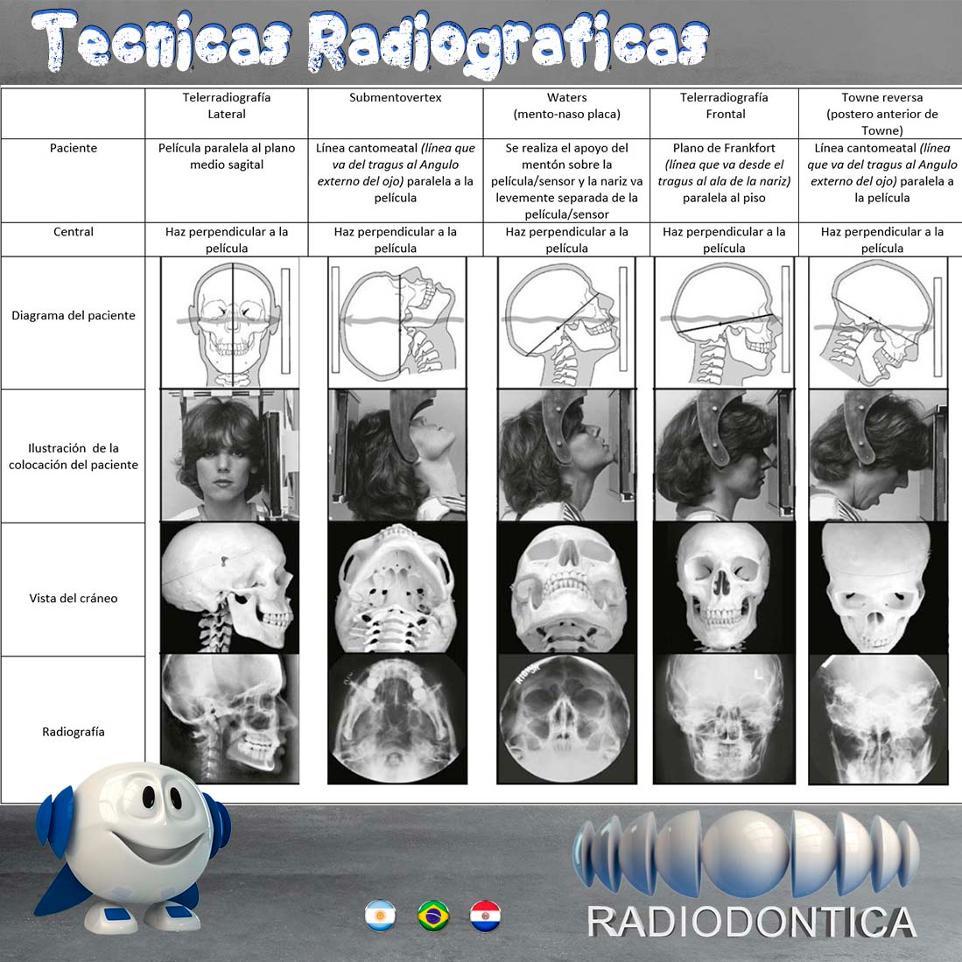

La presentación de casos radiográficos, permite la visualización de patologías que son muy difíciles de ver en la clínica, ya que muchos de ellos son hallazgos radiográficos. Además permite ver y refrescar clasificaciones y conceptos muchas veces estudiados. La presentación de los mismos no incluyen datos personales, mas que edad y sexo, que suelen ser importantes para ver la correlación entre la patología, su aparición o forma de presentación.

Esto también refleja las patologías que aquejan a los pacientes de nuestra región, y trata de ser un faro tanto para profesionales como alumnos que estudian dichas lesiones.